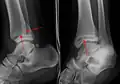

A triplane fracture of the ankle as seen on plain X-ray -

A triplane fracture of the ankle as seen on CT -

A triplane fracture of the ankle as seen on CT

- Triplane fractures are a special type of fracture that involves the immature skeleton. It has a coronal plane in the metaphysis, an axial plane in the physis, and a sagittal plane in the epiphysis.[15]